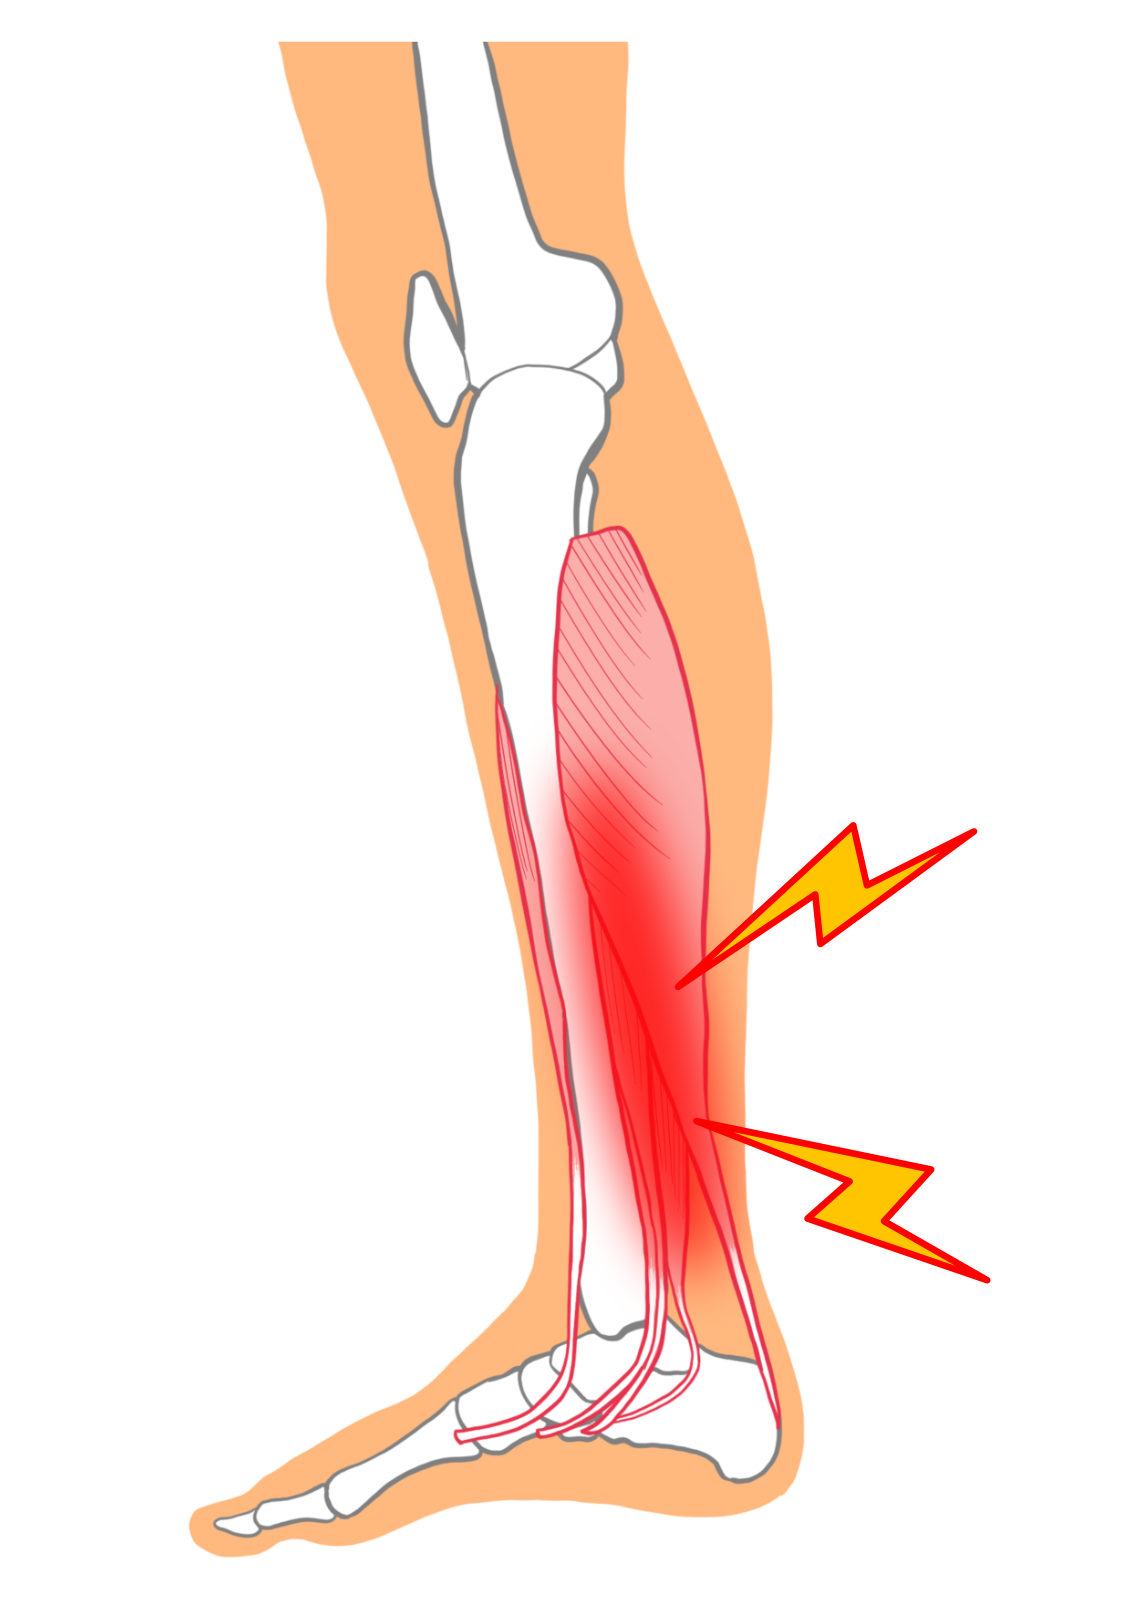

過労性脛部痛、脛骨疲労性骨膜炎または脛骨過労性骨膜炎とも呼ばれており、

ランニングやジャンプなどを過度に繰り返すことによって、

主に前脛骨筋、後脛骨筋、長趾伸筋、長趾屈筋などの付着部が引っ張られることによって起こる骨膜の炎症です。

なお前脛骨筋、長趾伸筋などの脛骨前面外側の筋肉によって引き起こされるのを全外側シンスプリント、

後脛骨筋、長趾屈筋などの脛骨後面内側の筋肉によって引き起こされるのを後内側シンスプリントと呼びます。

★シンスプリントの症状

初期の段階では運動時もしくは運動後に脛骨内側の中央から下方3分の1にかけてズキズキとした痛みや圧痛が生じます。

症状が進行すると安静時にも痛むようになり、次第に歩行困難になります。